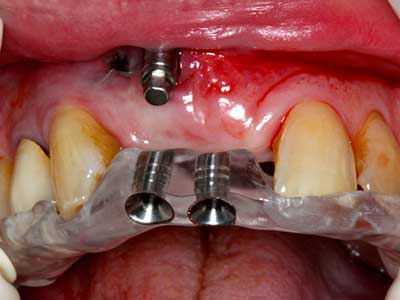

La piezochirurgia presenta altri vantaggi per quanto riguarda la raccolta di blocchi ossei. Oltre all'elevata precisione dell'osteotomia appena descritta, l'utilizzo di puntine per sega molto sottili permette di minimizzare in maniera significativa la perdita di materiale. È molto probabile che si verifichi una maggiore perdita di materiale durante la raccolta utilizzando puntine di strumenti più spessi, in particolare delle frese Lindemann (Lakshmiganthan, Gokulanathan et al. 2012). La separazione basale, necessaria in particolare per i trapianti di blocchi nella zona retromolare, viene semplificata grazie a seghe specificatamente progettate di forma rettangolare; di conseguenza la piezochirurgia è considerata una procedura precisa, semplice e sicura per la raccolta di blocchi di osso nella zona retromolare (Happe 2007) (figg. 1-12).

Indicazione: incisione ossea

Il tessuto osseo non è semplicemente una struttura minerale, ma contiene anche una percentuale significativa di fibre di collagene. Ciò significa che non possiede solo una buona forza di compressione, ma anche un certo livello di flessibilità che è possibile sfruttare durante l'esecuzione degli accrescimenti di osso. Nella procedura di espansione classica con incisione ossea, la cresta alveolare atrofizzata viene incisa longitudinalmente ed espansa con cautela dopo aver raggiunto una profondità di osteotomia adeguata (figg. 13-16), idealmente senza una sostanziale rimozione del periostio (Brugnami, Caiazzo et al. 2014, Stricker, Fleiner et al. 2014). I sistemi a piastra e vite con distanza di espansione incrementale si sono dimostrati efficaci nella separazione delle due lamelle ossee restando al di sotto della soglia di frattura. In generale, sono richieste larghezze dell'osso residuo di almeno 3-4 mm (Chiapasco, Zaniboni et al. 2006) per garantire un'adeguata flessibilità e una copertura sufficiente dell'osso per gli impianti futuri. Se necessario, un'osteotomia di rilascio verticale su uno o più lati può migliorare la flessibilità. Una combinazione con ulteriori tecniche di accrescimento, in particolare dal lato buccale, è stata descritta come un'alternativa alla tecnica classica.

La procedura di incisione è particolarmente atraumatica e non comporta una perdita significativa di dimensione durante l'utilizzo delle seghe piezoelettriche, così come non si notano differenze rilevanti tra impianti in mandibole incise e impianti in una cresta alveolare senza deficit osseo (Chiapasco, Zaniboni et al. 2006, Danza, Guidi et al. 2009). Una sufficiente irrigazione continua è essenziale, tuttavia, in particolare con incisione profonda e localmente ristretta, per prevenire la sollecitazione termica nelle regioni apicali dell'osteotomia.